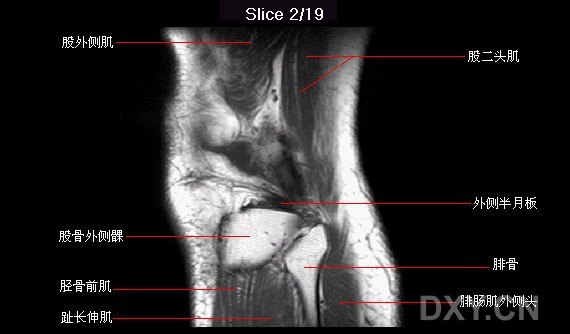

正常膝关节矢状位MRI